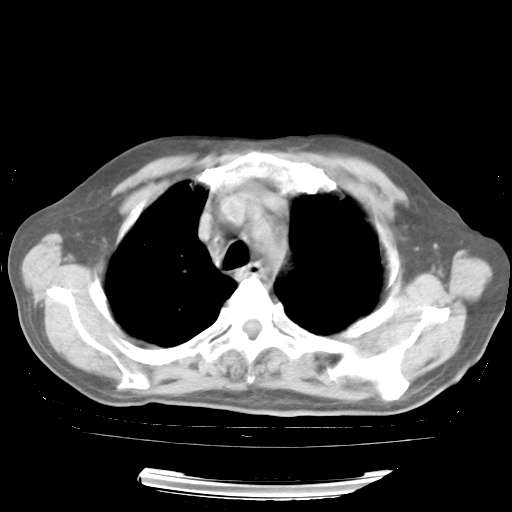

4月28日肺部CT——再次出现类似去年5月9日——透光度降低,“间质性”改变。

4月28日肺部CT——再次出现类似去年5月9日——磨玻璃样、间有“粟粒样”改变。

个人阅读4.14日肺部CT平扫:纵隔窗无异常,但肺窗示:双下肺内、后基底段有片絮状侵润影,部位以后基底段为著,以间质改变为主,呈急性肺泡炎征像,和首次住院影像学有相似之处。仅是个人读片,明日请相关专家再读片哈。其它建议同上。

1、108#的是4月14日的胸部CT(发此贴时还没看着28日的CT)。14日的胸部CT其实已经出现改变(如108#所述),个人认为28日的胸部CT除纵膈窗疑似有双侧胸膜增厚或少量胸积液(可行胸部B超明确)外,与4月14日对照病变有所加重;2、已经给予“异烟肼、利福平、乙胺丁醇”抗痨治疗?如果是,甲强龙80mg可缓慢减量;如果环磷酰胺已停用,暂不使用;3、中性粒细胞92%,明显升高,目前体温情况?注意合并细菌感染可能,使用左氧氟沙星情况下,是否联用B-内酰胺类抗菌药物?另外是查免疫全套非风湿全套。